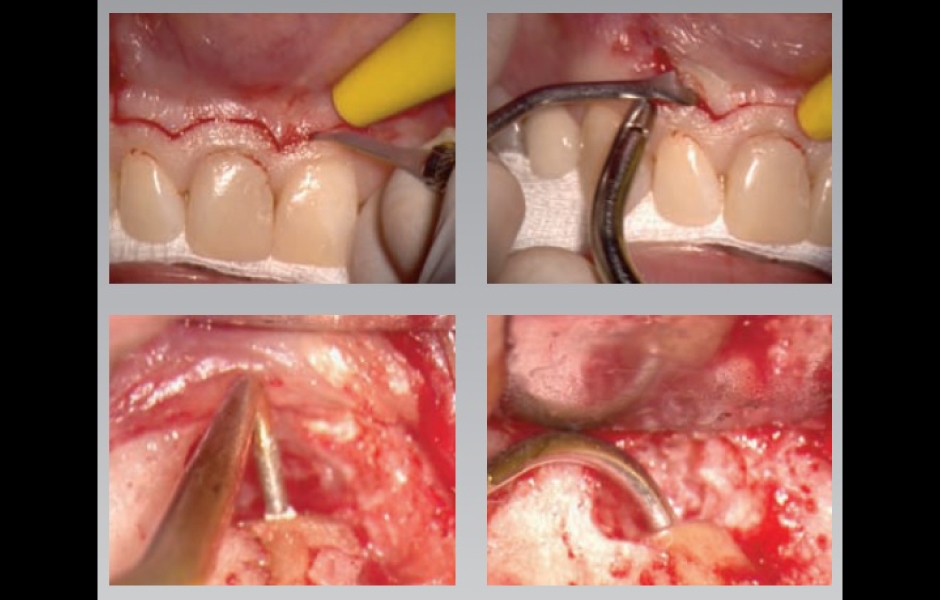

Jeho koncepty jsou postavené na jednoduše pochopitelných, snadno reprodukovatelných postupech, které přinášejí vysoce prediktabilní výsledky i v těch nejsložitějších klinických případech.

Jak říká Dr. Castellucci: "Nebojte se chirurgie, může vás elegantně zachránit v jinak neřešitelných situacích".

Součástí programu je také výjimečně intenzivní celodenní hands-on kurz endodontické mikrochirurgie. Nejintenzivnější praktický kurz, který byl u nás v tomto oboru organizován, si klade za cíl účastníky doslova vyždímat na retrográdním mikrochirurgickém ošetření až čtyř (!) reálných zubů, od řezáků až po horní i dolní moláry. Cílem organizátora je udělat z hands-on kurzu nezapomenutelný intenzivní zážitek, pro který nemusíte jezdit až do Florencie.

Teoretický koncept prediktabilní mikrochirurgické endodoncie od A do Z, výjimečně intenzivní hands-on kurz s operačním mikroskopem a na skutečných zubech včetně molárů.

Dr. Castellucciho přístup k mikrochirurgické endodoncii je přímočarý a čistý

…a přináší bezpečné a prediktabilní výsledky v podobě úspěšného hojení